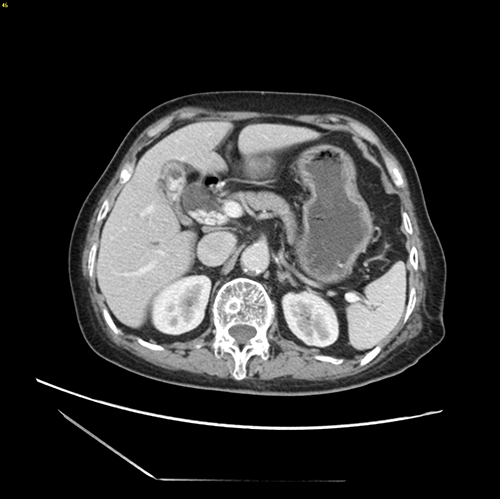

肝内外胆管结石-腹腔镜左半肝切除、 胆囊切除、胆总管切开取石、T管引流